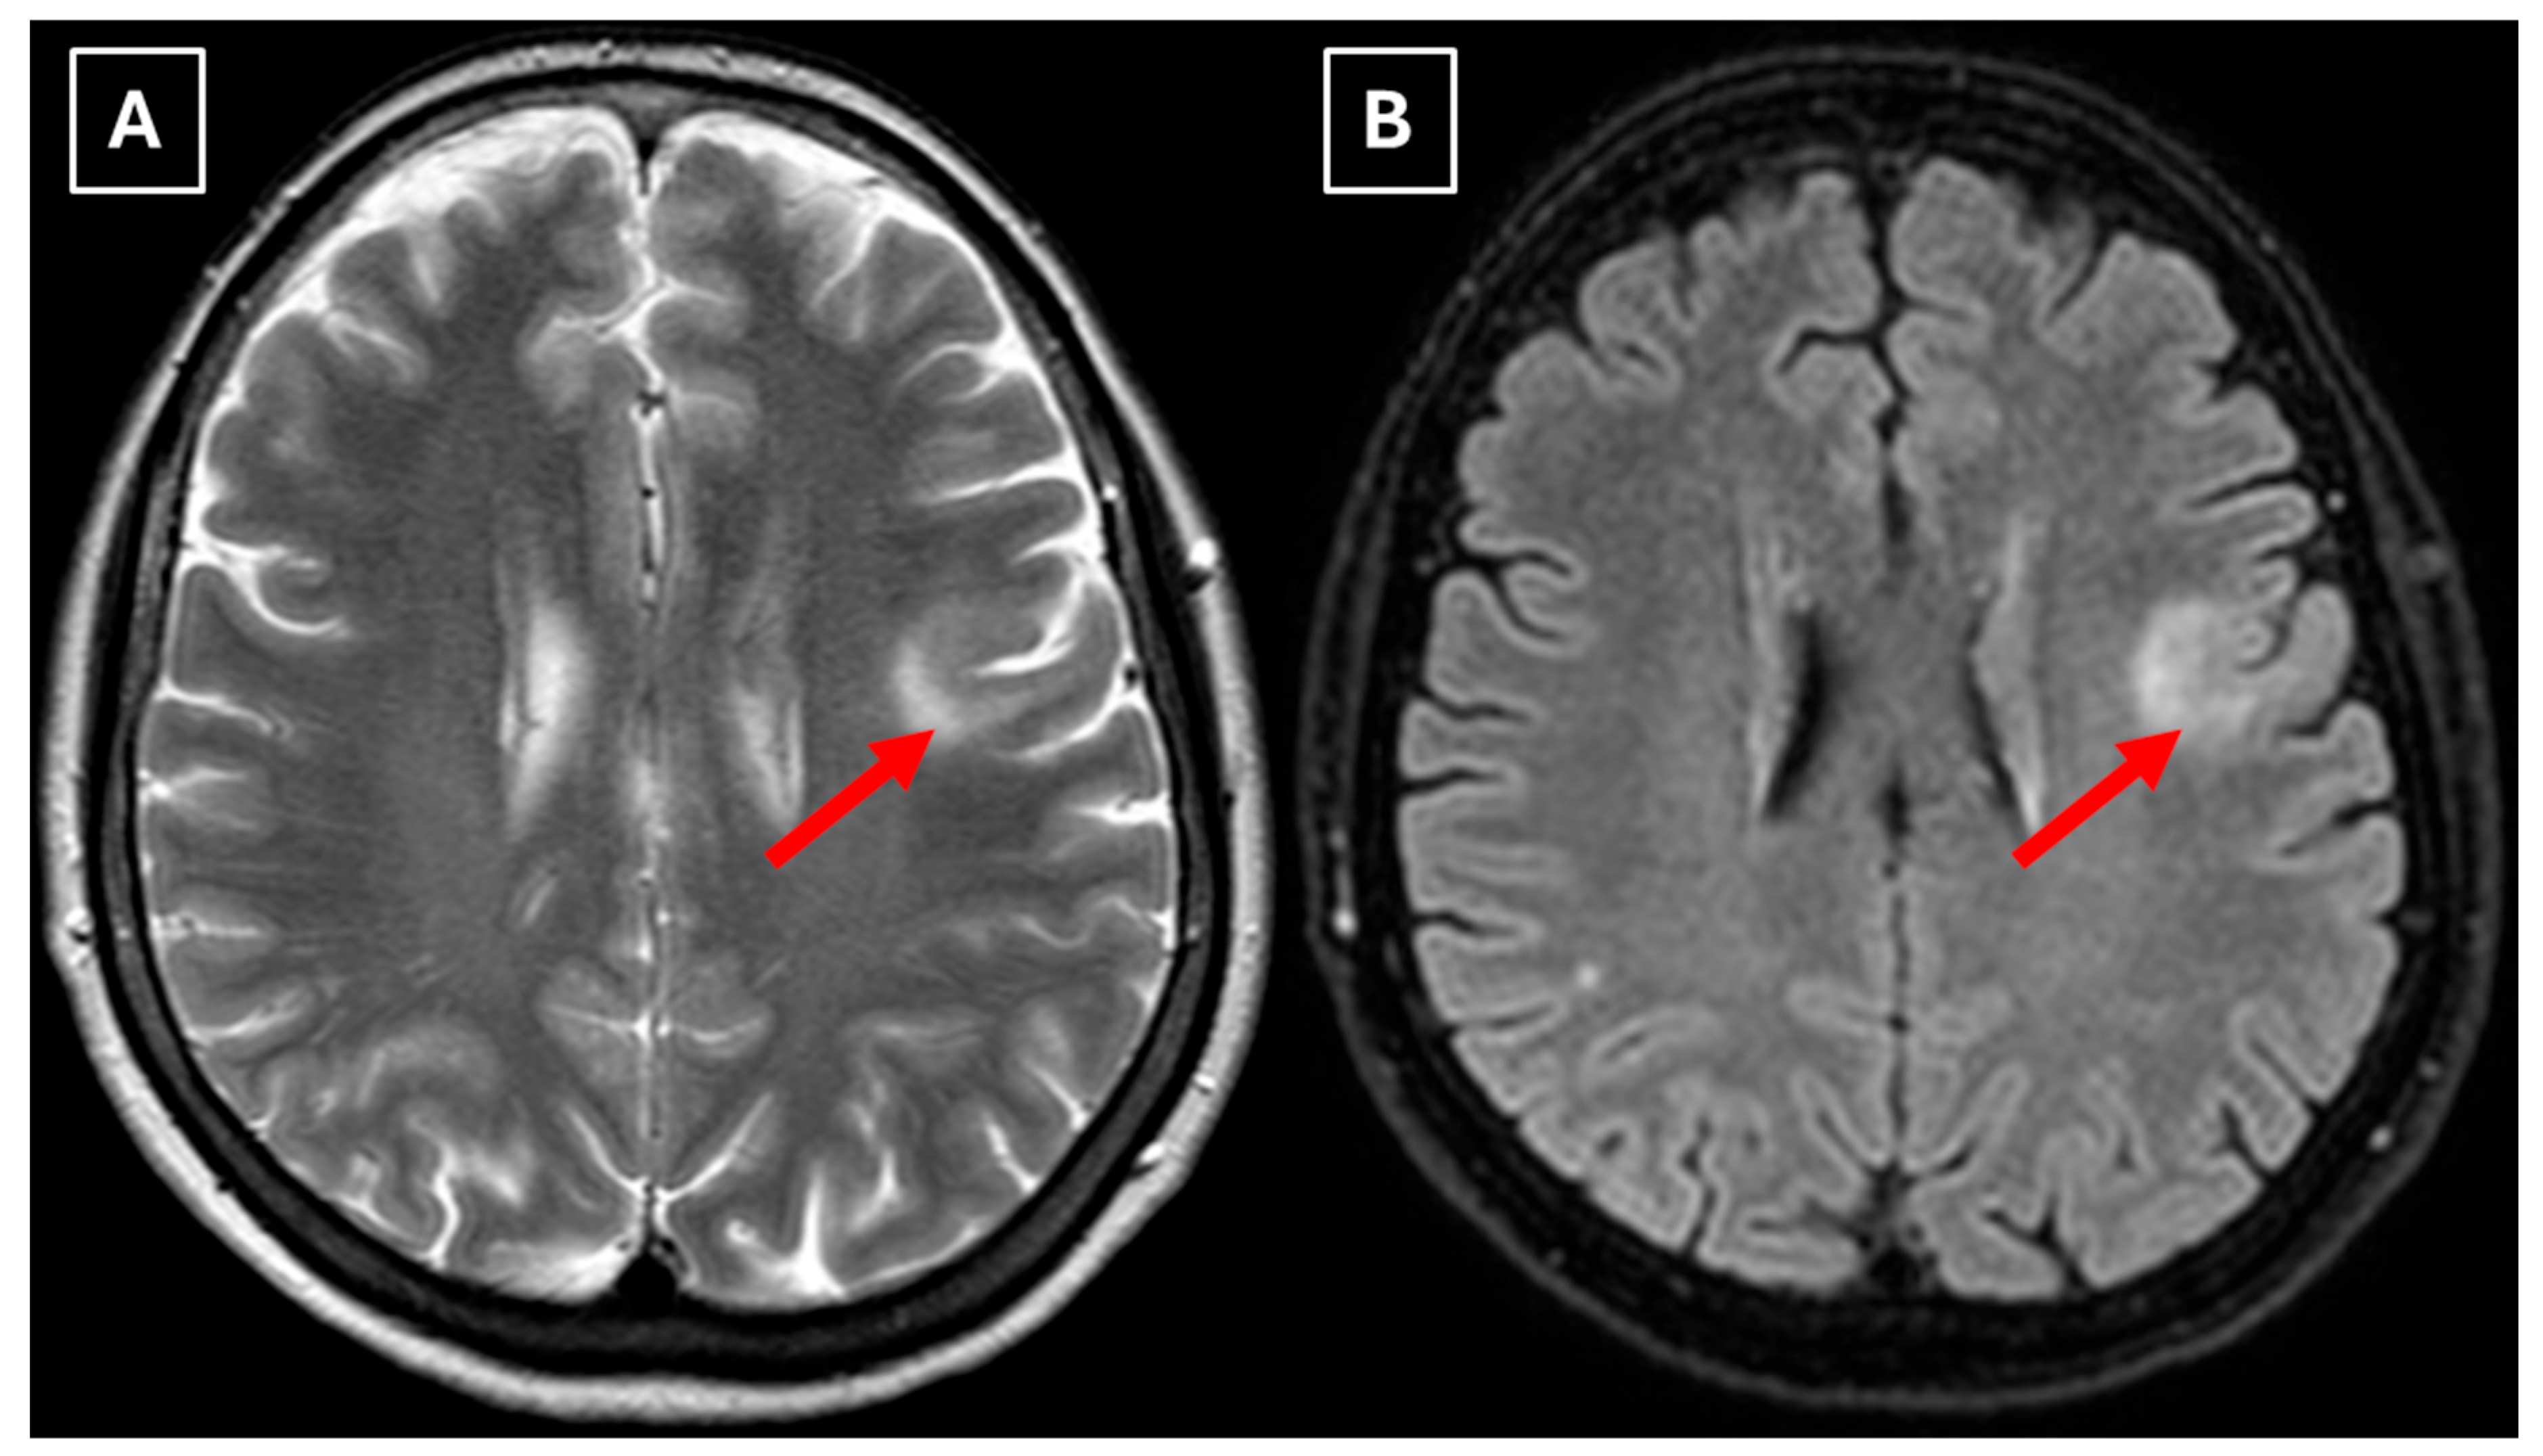

One week later, a brain MRI with intravenous contrast was performed, which revealed a well-defined subcortical lesion approximately 3.5 cm in diameter in the posterior basal parts of the left frontal lobe, accompanied by perifocal edema and sulcal effacement (Figure 2). No pathological contrast enhancement was observed (Figure 3). No other white matter lesion was identified to suggest signs of leukodystrophy, and no hemosiderin deposits were identified in the brain or meninges (Figure 3). Given the T2/FLAIR mismatch (Figure 2), the most likely diagnosis was infiltrative low-grade astrocytoma. The patient received mannitol anti-edema therapy, resulting in clinical improvement and a reduction in neurological symptoms. The case was discussed by a multidisciplinary team (neurologist, neurosurgeon, radiologist, oncologist, and pathologist). Surgical treatment and morphological verification of the tumor were recommended. A day later the patient was discharged from the hospital in a stable condition, with a recommendation to be admitted to the neurosurgery department for surgery in two weeks. She was prescribed dexamethasone tablets of 0.5 mg twice daily on an outpatient basis.

Figure 2. MRI scan of the brain. (A): Axial T2-weighted sequence shows a well-defined, homogenous, hyperintense mass-like lesion in the inferior part of the left frontal lobe, with involvement of the juxtacortical white matter and relative sparing of the cortical gray matter. The lesion measured 37.34 mm × 34.85 mm (AP × LL). Additionally, there is incomplete perifocal edema surrounding the lesion, extending to the white matter and away from the cortex. (B): Axial FLAIR sequence shows the lesion with a relatively more hypointense center and a hyperintense peripheral rim at the lesion margins. A T2/FLAIR mismatch sign was observed, making the likely diagnosis an infiltrative low-grade astrocytoma. All MRI images were acquired with the Philips “Ingenia Ambition X” 1.5T system. Red arrow—indistinct formation, yellow arrow—perifocal vasogenic edema.

Secondly, the presence of a T2/FLAIR mismatch sign in this case, which initially was suggestive of a low-grade astrocytoma, adds diagnostic complexity and underlines the potential for radiological overlap between TDLs and IDH-mutant astrocytomas. One proposed pathophysiological explanation of this overlap is the presence of microcysts and enlarged intracellular space with fluid characteristics similar to cerebrospinal fluid [12,15]. Such components may also be present in both low-grade gliomas and TDLs, resulting in marked T2 hyperintensity and relative suppression on FLAIR sequences. Additionally, this apparent overlap with TDLs may be further explained by shared microstructural changes such as severe myelin loss, reactive gliosis, and accumulation of macrophages, as well commonly seen edema, similarly producing an imaging appearance of (IDH)-mutant 1p/19q non-coded astrocytoma [16]. Studies have also shown that low-grade astrocytomas are among the most frequent histopathological misdiagnoses of TDLs, reflecting their morphological similarity [1]. However, it remains uncertain whether analogous microstructural or fluid-dynamic mechanisms take place in TDLs, since there is no research available that directly investigated the histopathological correlates of the T2/FLAIR mismatch sign in TDLs; in addition, this sign is not mentioned in MRI features of demyelinating diseases. Therefore, its application, specificity, and sensitivity for TDL diagnosis are not established. The underlying mechanisms of TDL pathophysiology also remain incompletely understood, but immune-mediated inflammation with massive infiltration of macrophages and lymphocytes, dysregulated astrocyte signaling, complement activation arising as part of multiple sclerosis leading to exaggerated CNS immune responses, and medication effects such as fingolimod use, as well as its cessation, have all been proposed as contributing factors [6,10,11].

In this case, despite the presence of a T2/FLAIR mismatch sign (Figure 2), several imaging characteristics were more suggestive of a TDL rather than IDH-mutant astrocytoma. The lesion was located in juxtacortical white matter and had cortical sparing, which is unusual for IDH-mutant astrocytomas, since they typically have been shown to infiltrate and expand the cortex. The diffusion restriction at the lesion margin with centrally elevated ADC values was more consistent with reported DWI findings of TDLs and contrasted with the central restriction often seen in gliomas. The mass effect was mild in comparison to the overall lesion size, favoring demyelination rather than neoplasm in this case. Additionally, the lesion had a central vein sign, as described above, a radiological sign supportive of inflammatory demyelination. The combination of cortical sparing, peripheral diffusion restriction, mild mass effect, and the appearance of central vein sign represented strong features that raised suspicion of a tumefactive demyelination lesion.